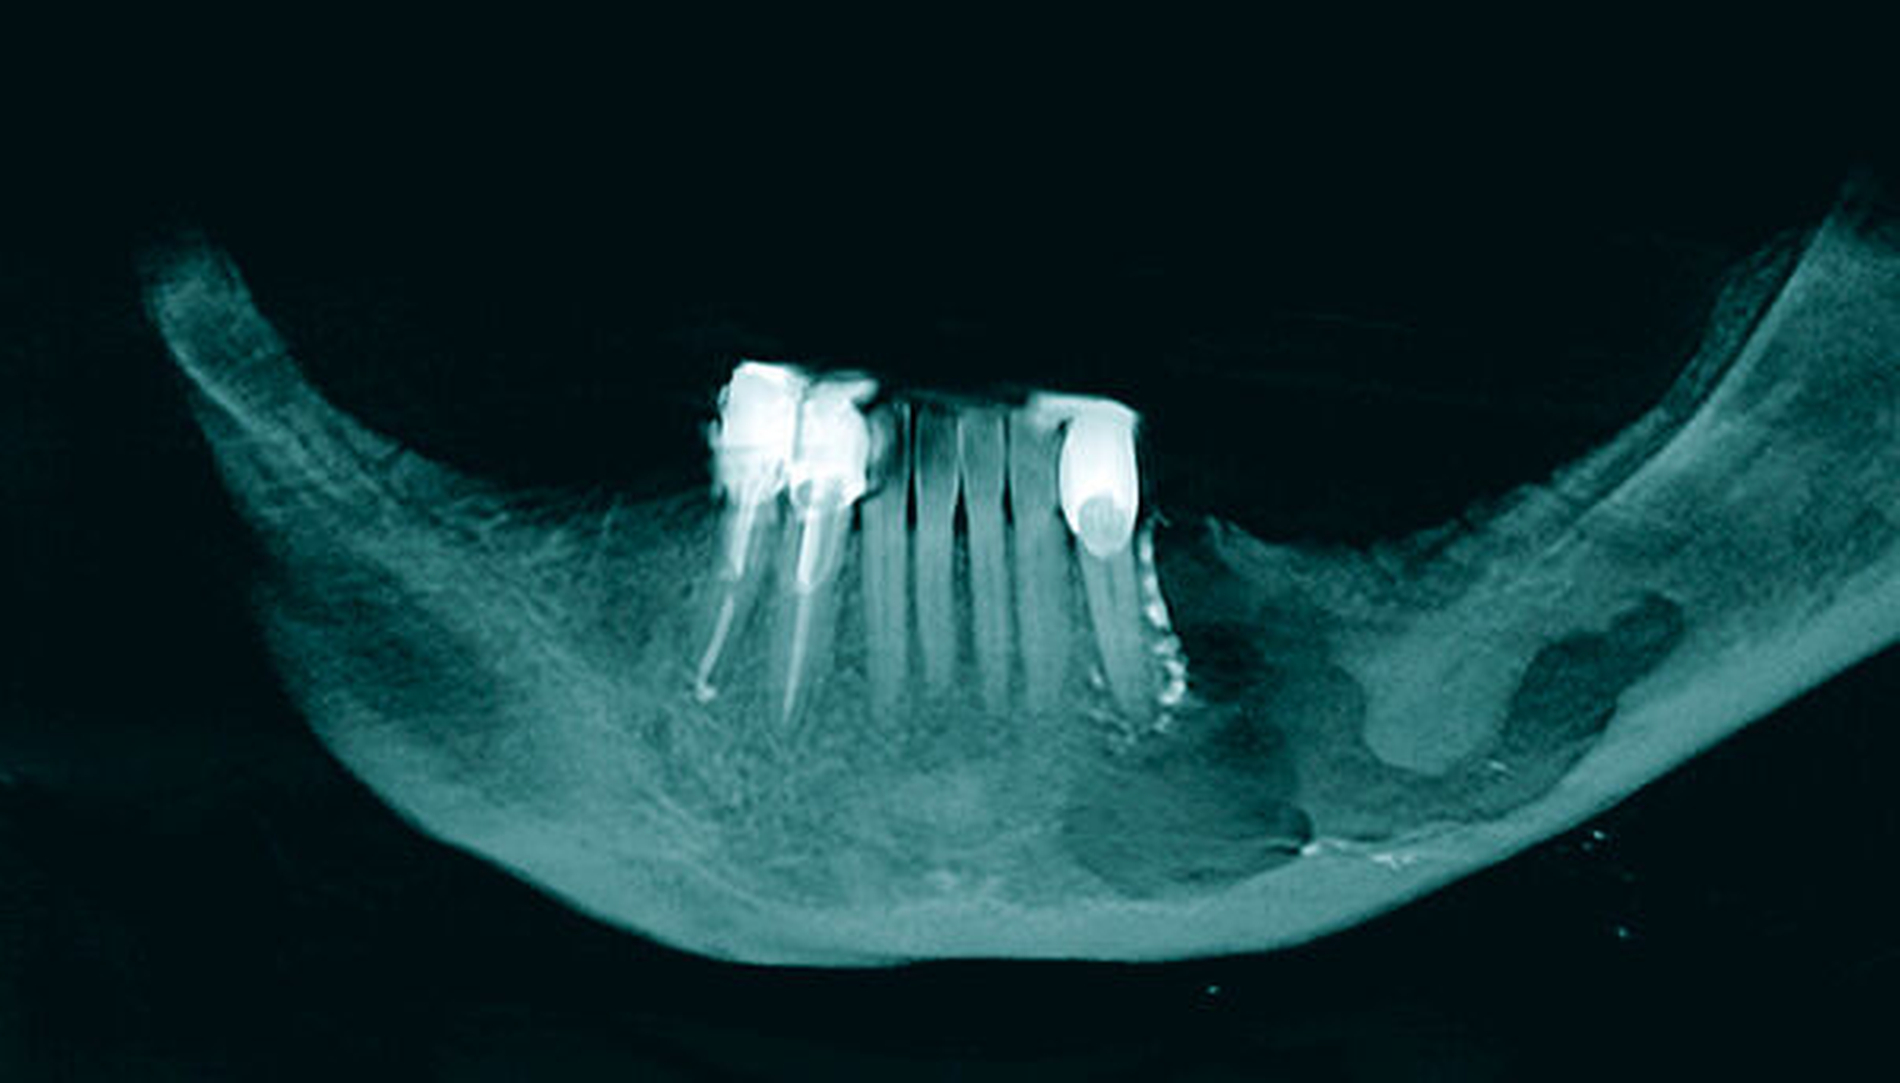

Radiologisch zeigt die erste Panoramaschichtaufnahme die präendodontische Ausgangssituation mit einer metalldichten Verschattung in regio 036. Die postendodontische Panoramaschichtaufnahme stellt die Wurzelfüllung mit dem überpressten Sealer periapikal und in Höhe des Mandibularkanals links dar (Abbildungen 1 und 2).

Zur Beurteilung der Überfüllung wurde alio loco eine DVT erstellt, die den Sealerverlauf in allen Ebenen abbildet. Der Austritt des Sealers nach lingual, nach bukkal und im Mandibularkanal wird hier dreidimensional präzise dargestellt (Abbildungen 3 und 4).